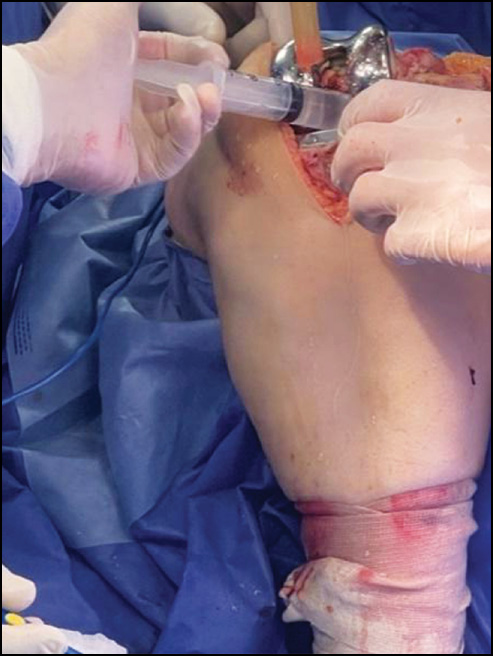

Starting with the first knee, a medial parapatellar approach was carried out.

The patella was the focal point of a longitudinal midline skin incision. The parapatellar retinacular incision was extended proximally along the length of the quadriceps tendon, leaving a 3–4 mm portion of the vastus medialis tendon for subsequent closure. The incision was extended 3–4 cm along the medial border of the patellar tendon to the anteromedial surface of the tibia, encircling the medial side of the patella. The anteromedial capsule and deep medial collateral ligament were subperiosteally elevated off the tibia to the posteromedial corner of the knee, exposing the medial side of the knee (Fig. 1).

Fig. 1. Medial parapatellar approach: skin incision (a) and deep dissection (b).

Рис. 1. Медиальный парапателлярный подход: разрез кожи (a) и глубокое рассечение (b).

Finally, if appropriate size was determined, an extensive wash (Fig. 8) was conducted to remove soft tissue and bony debris, and then cement was applied, and the chosen implant was cemented and applied in position (Fig. 9–10).

Fig. 8. Washing and suctioning prior to final implant insertion.

Рис. 8. Промывание и отсасывание перед окончательной установкой имплантата.